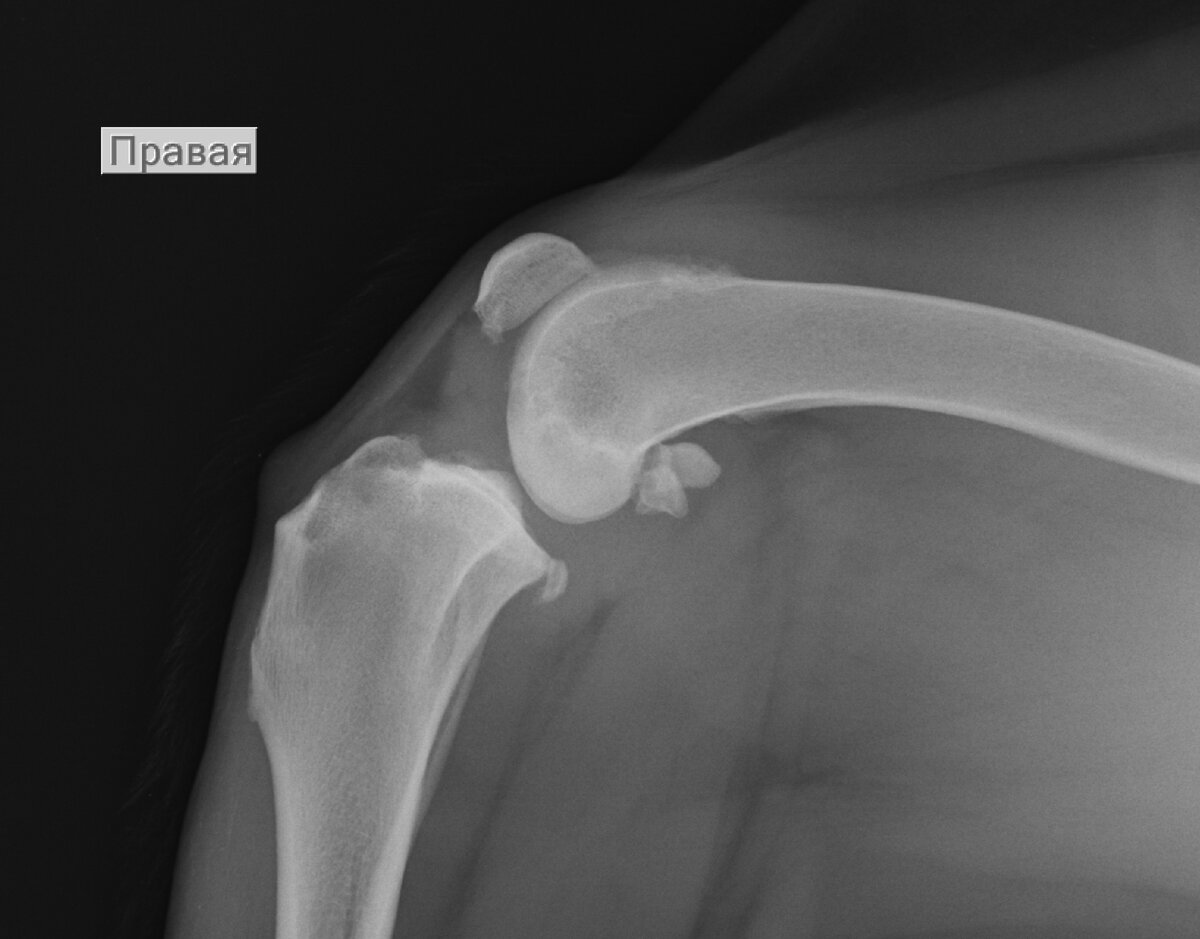

Начальные признаки остеоартрита у алабая на фоне нестабильности коленного сустава. Причина - разрыв передней крестовидной связки.

Иногда на снимке ты видишь сильную степень изменения в суставе, а собака может совсем не хромать или незначительно. А у пациентов с начальной степенью практически нет изменений на рентгеновском снимке, а они совсем не пользуются конечностью.